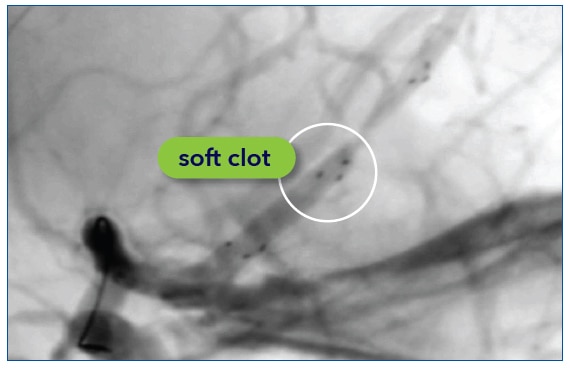

- Evaluate clot composition through body marker integration into the clot

- Visualize the expansion and compression of the stent to help identify clot characteristics8